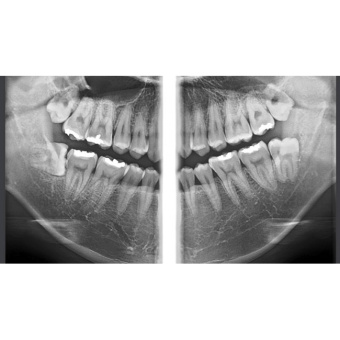

Ортопантомограф RAYSCAN является передовым диагностическим оборудованием, в котором применяются 2 сенсора: высококачественный плоский сенсор HAMAMATSU (Япония) для панорамной съёмки и отдельный сканирующий сенсор, которые обеспечивают чёткое изображение с первого раза (даже волос и мягких тканей), последний имеет различные режимы сканирования.

Каждый пациент имеет разную форму и размер челюсти, поэтому для получения качественных снимков необходимо учитывать эти индивидуальные особенности. При настройке аппарата предусмотрены 7 анатомических режимов, которые позволяют быстро ввести параметры съёмки с учётом индивидуальности пациента (размеры тела пациента: крупный, нормальный или худой; размер челюсти: взрослый пациент или ребёнок; проекции: височно-нижнечелюстные суставы (ВНЧС) или верхнечелюстные пазухи (Синус).

- Стандартная панорамная.

- Панорамная съёмка широкой зубной дуги.

- Ортогональная проекция.